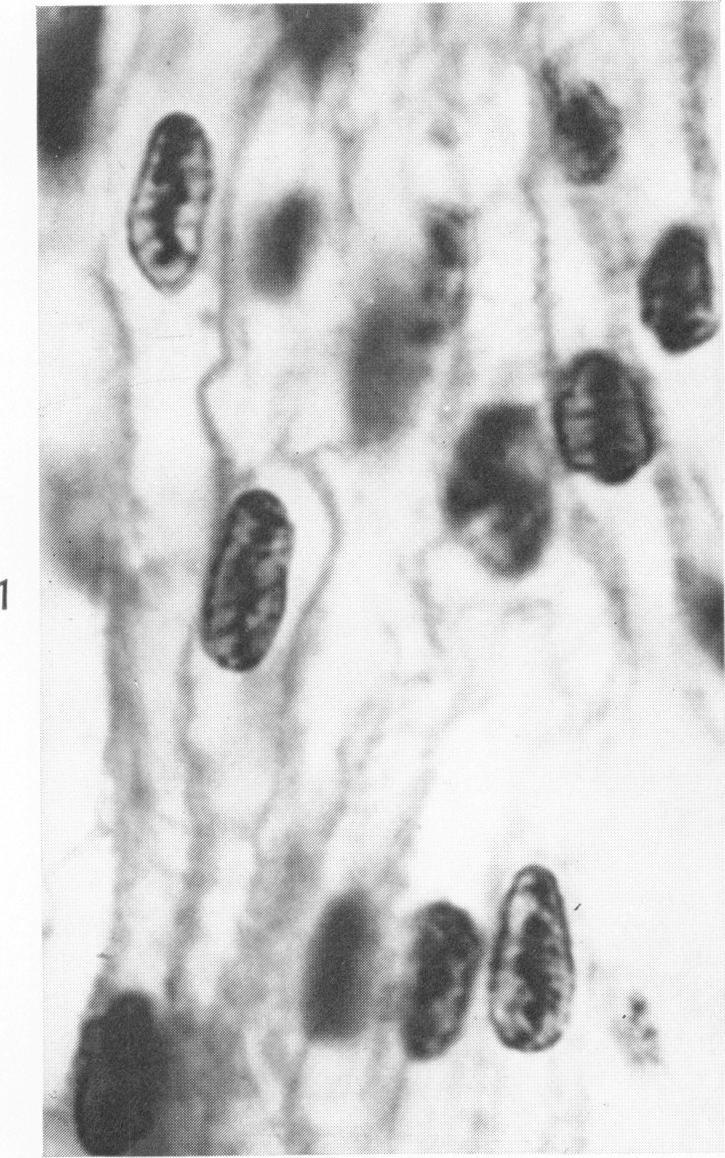

Occurrence of caterpillar nuclei within normal immature and normal appearing and altered mature heart muscle cells and the evolution of Anitschkow cells from the latter.

Am J Pathol. 1966 Jun;48(6):931-57.